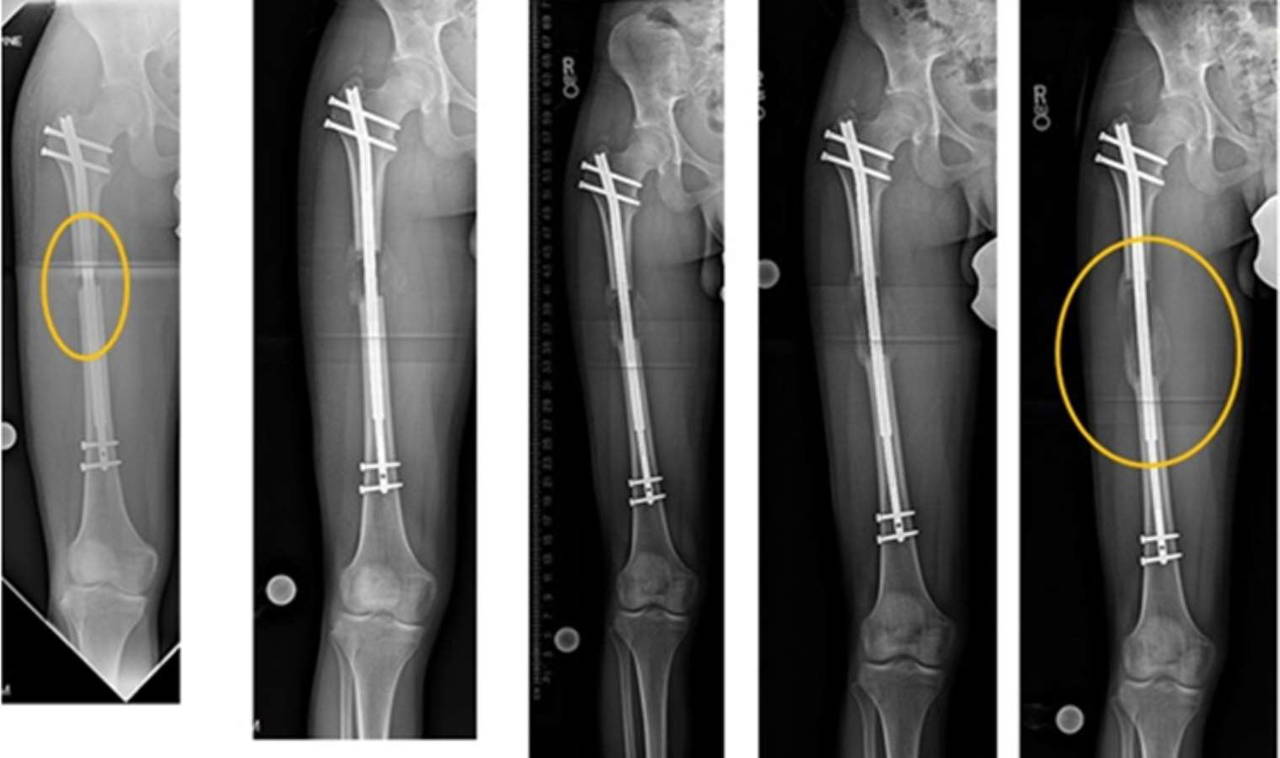

"Uzatma cihazının üzerine yerleştirilen mıknatıs, cihazdaki dişliyi mekanik hale getirerek teleskopik çubuğu hareket ettirir. Mıknatıs, uzvun uzunluğunu artırmak için çubuktaki dişlileri döndürür."

Bununla birlikte, günde iki kez manyetik cihazı kullanmaya devam etmeniz gerekir. Söz konusu cihaz, bacağa yerleştirilen çubuğu günde yaklaşık 0,5 mm döndürür. Bunun ne kadar süreceği, boyunuzun ne kadar uzamasını istediğinize bağlıdır.

Kulağa diş tellerinin sıkılması gibi geliyor, ancak uzmanlar kıyaslanmayacak derecede daha acılı olduğunu garanti ediyor...